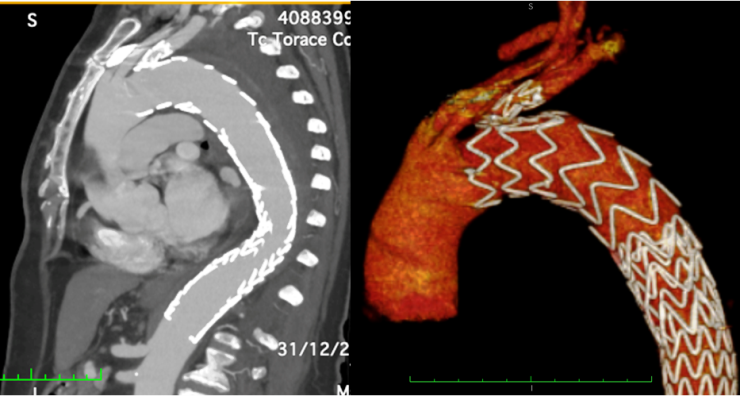

Chirurgia Vascolare del G.O.M.: utilizzato per la prima volta in Calabria un nuovo t ...

Le sindromi Aortiche Acute sono patologie gravate da un elevato tasso di mortalità e morbilità a causa della debolezza della parete aortica e del conseguente rischio ...